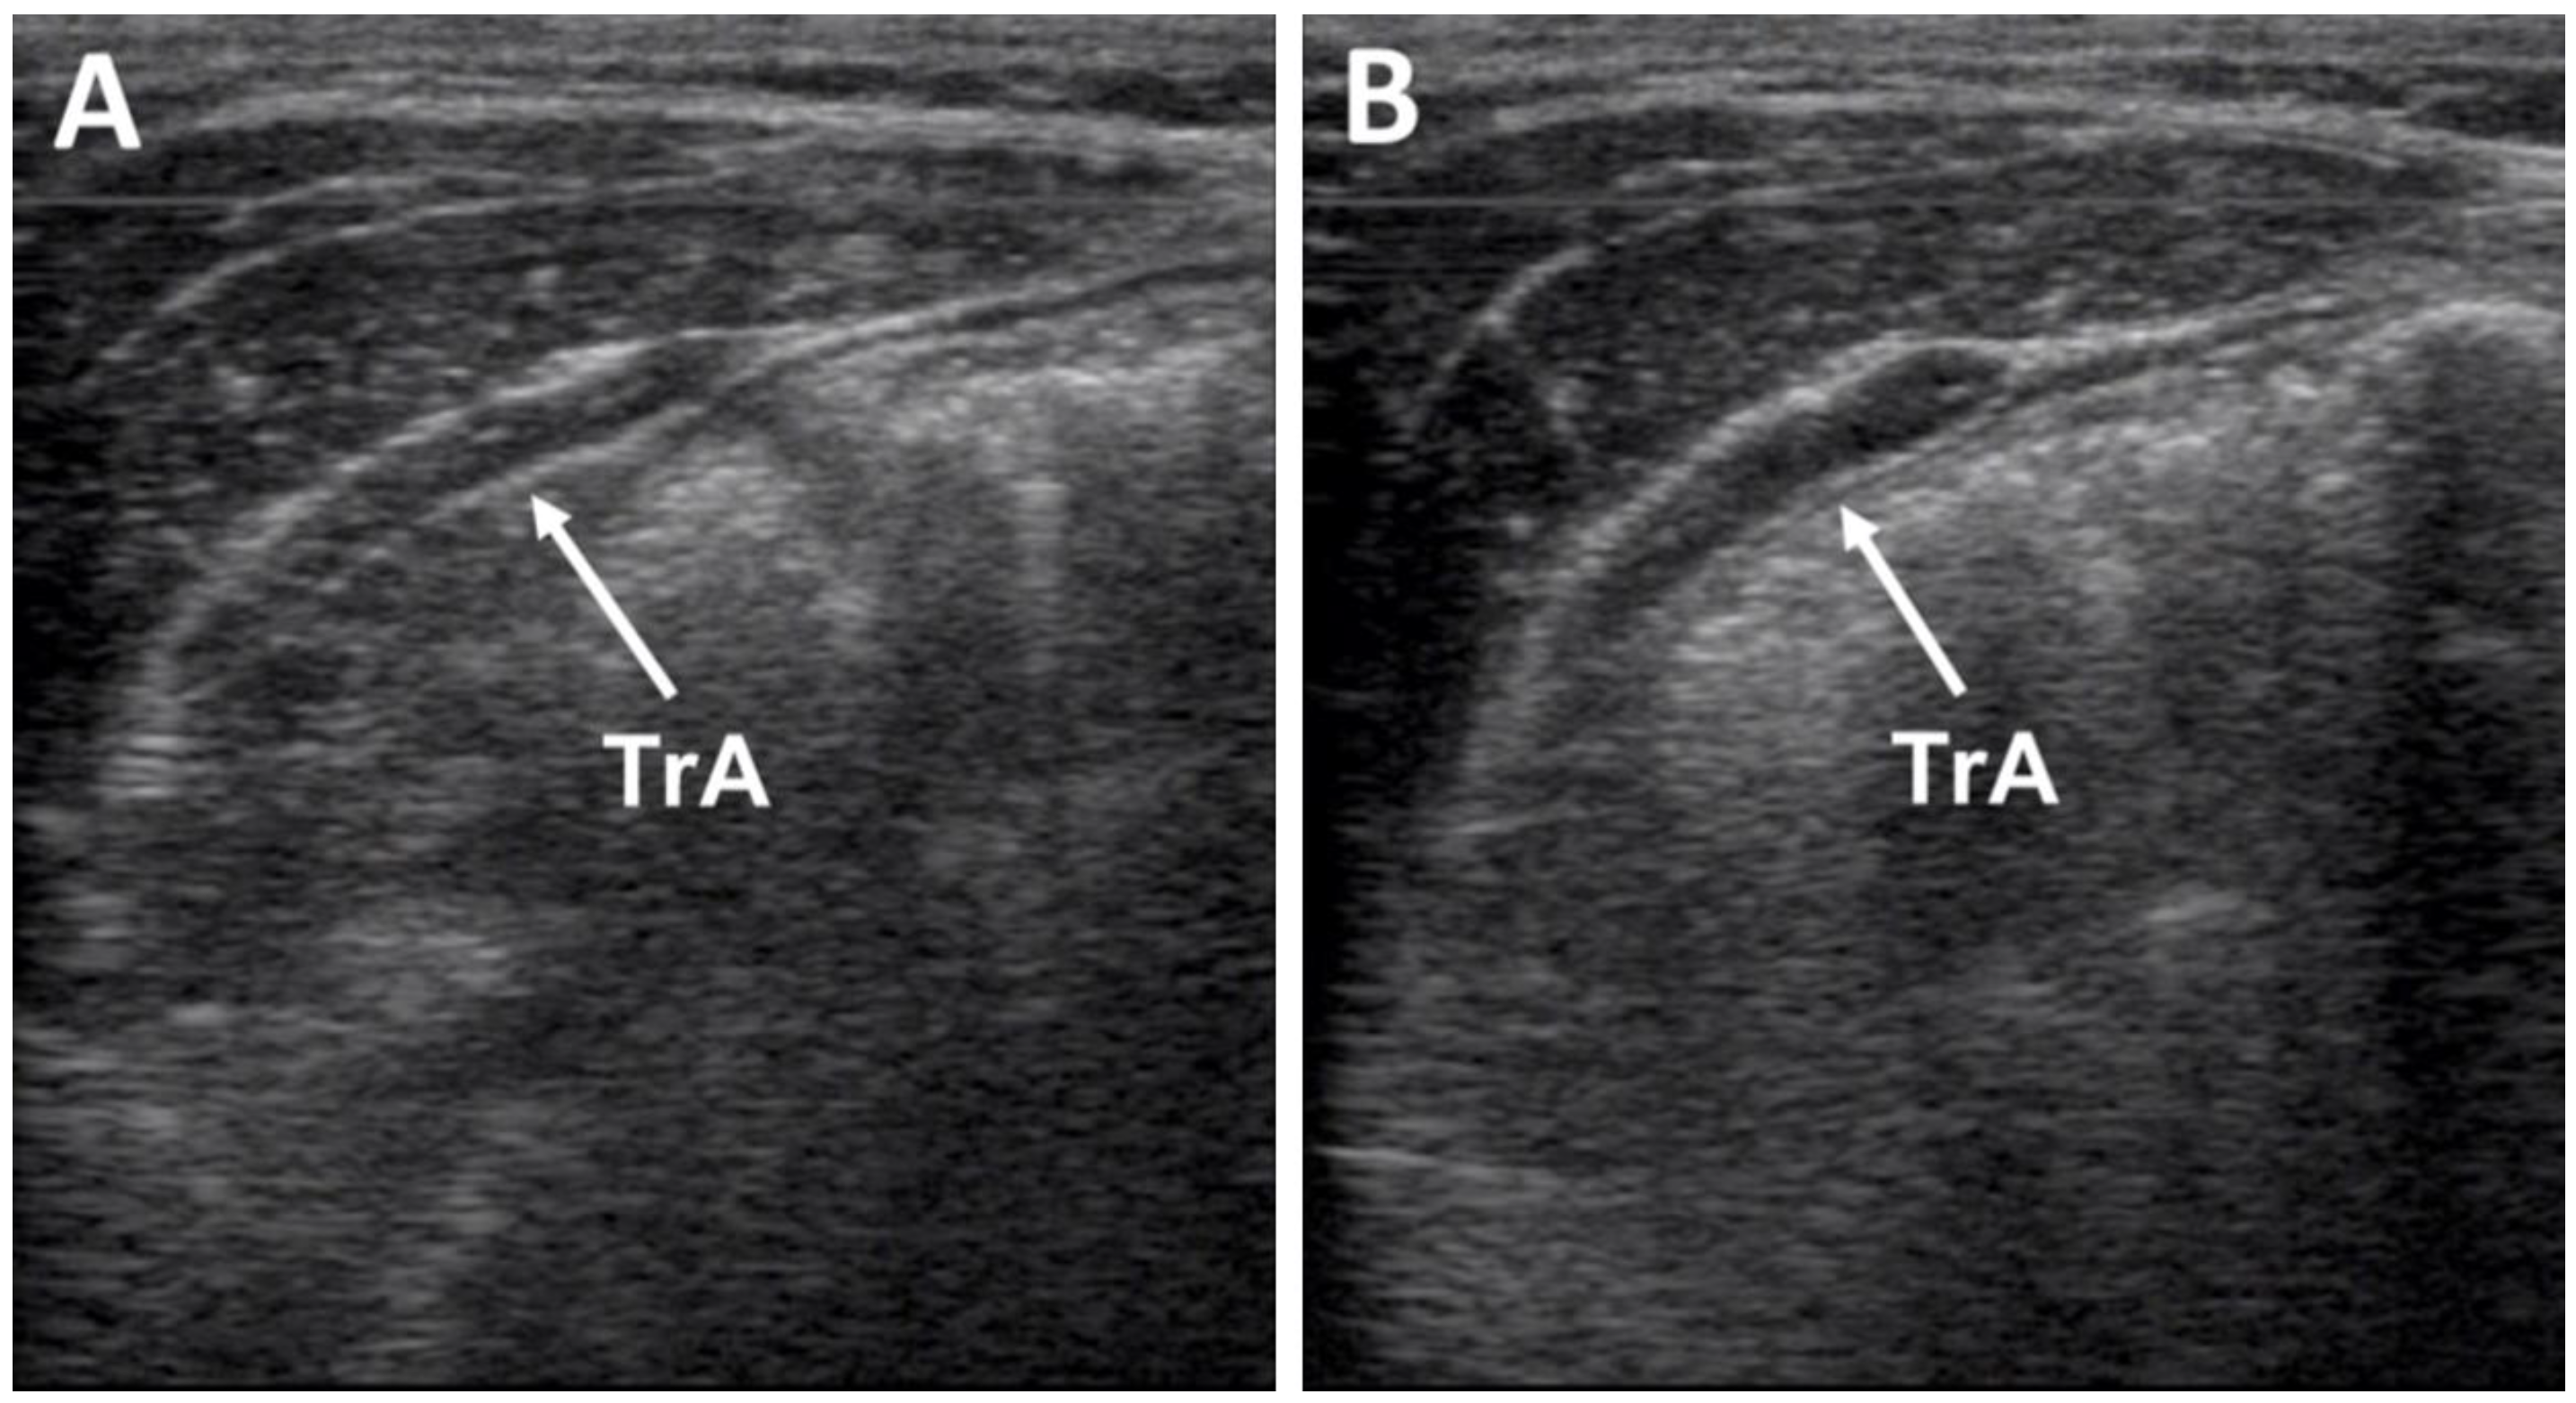

2.4. Muscle Thickness Measurements